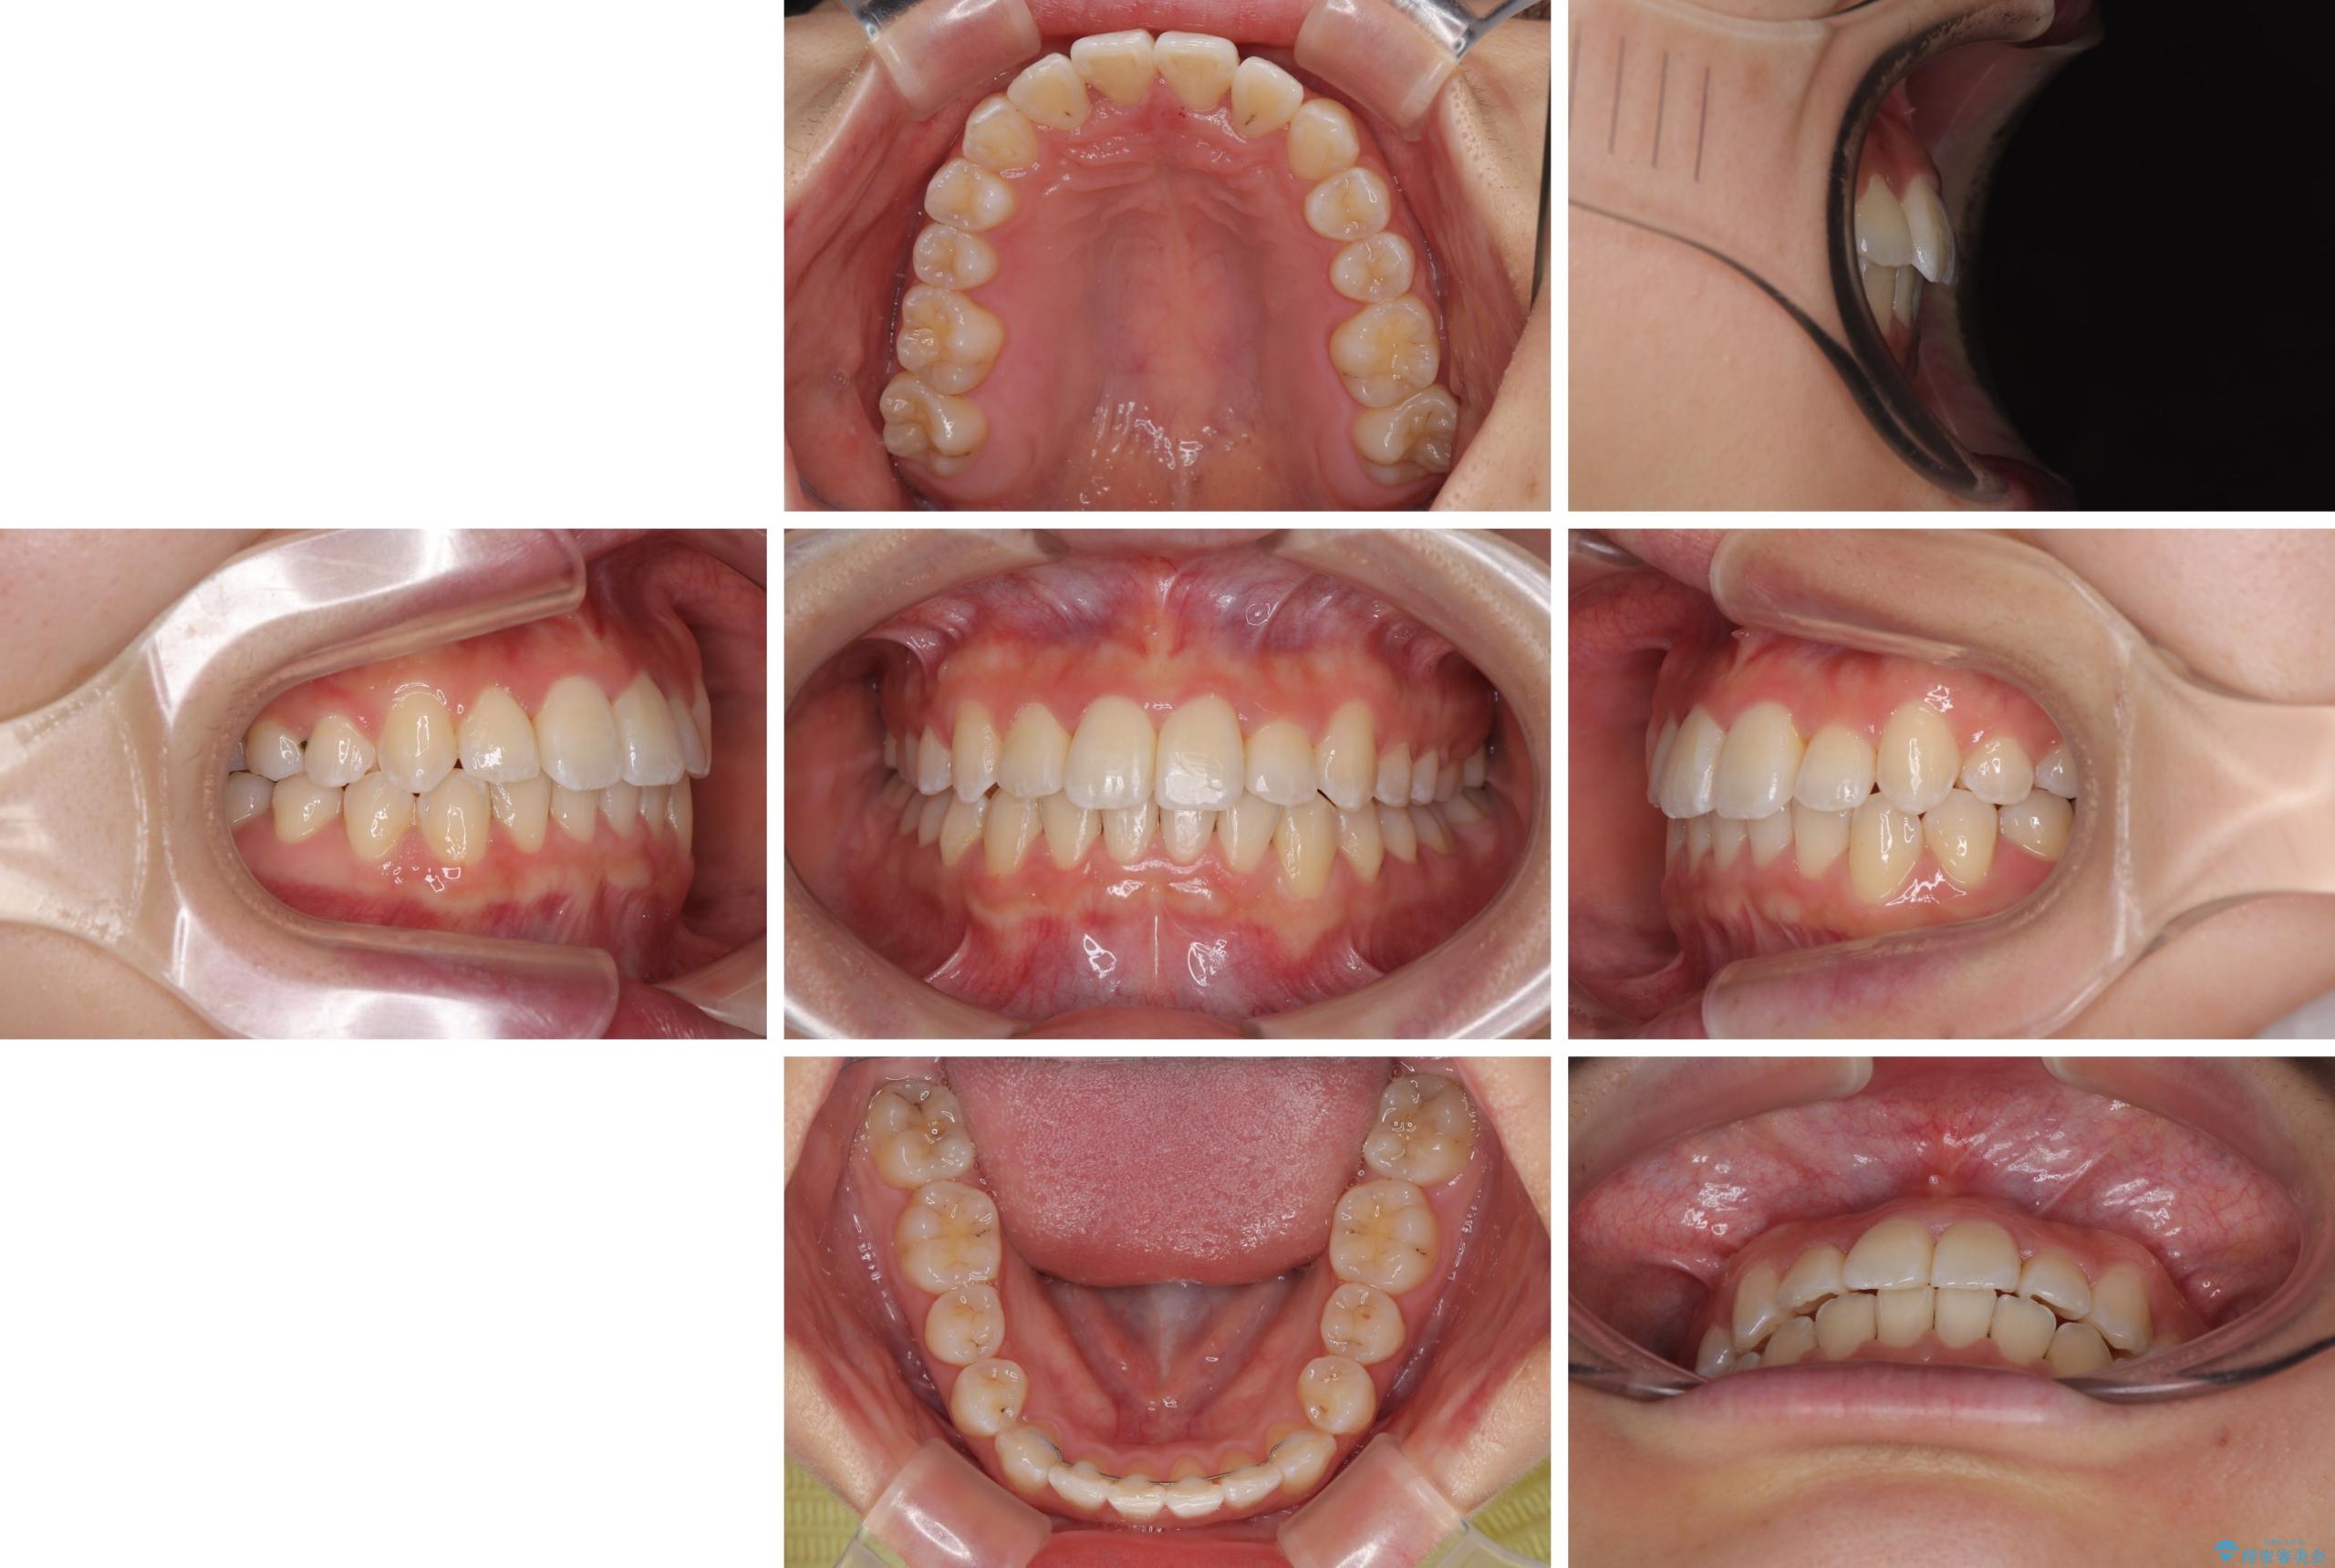

- 上顎前歯のクロスバイトを気にして来院された患者様です。

ワイヤー矯正でもマウスピース矯正でも対応可能でしたが、マウスピースによる自己管理に一切の自信がないとのことで、ワイヤー装置にて矯正治療を行うこととしました。

装置の外見を気にしていましたが、短期間で治療を終えることができるだろうと伝えると、安価であるメタルブラケットを選択されました。

想定通り、1年強で綺麗に仕上げることができました。